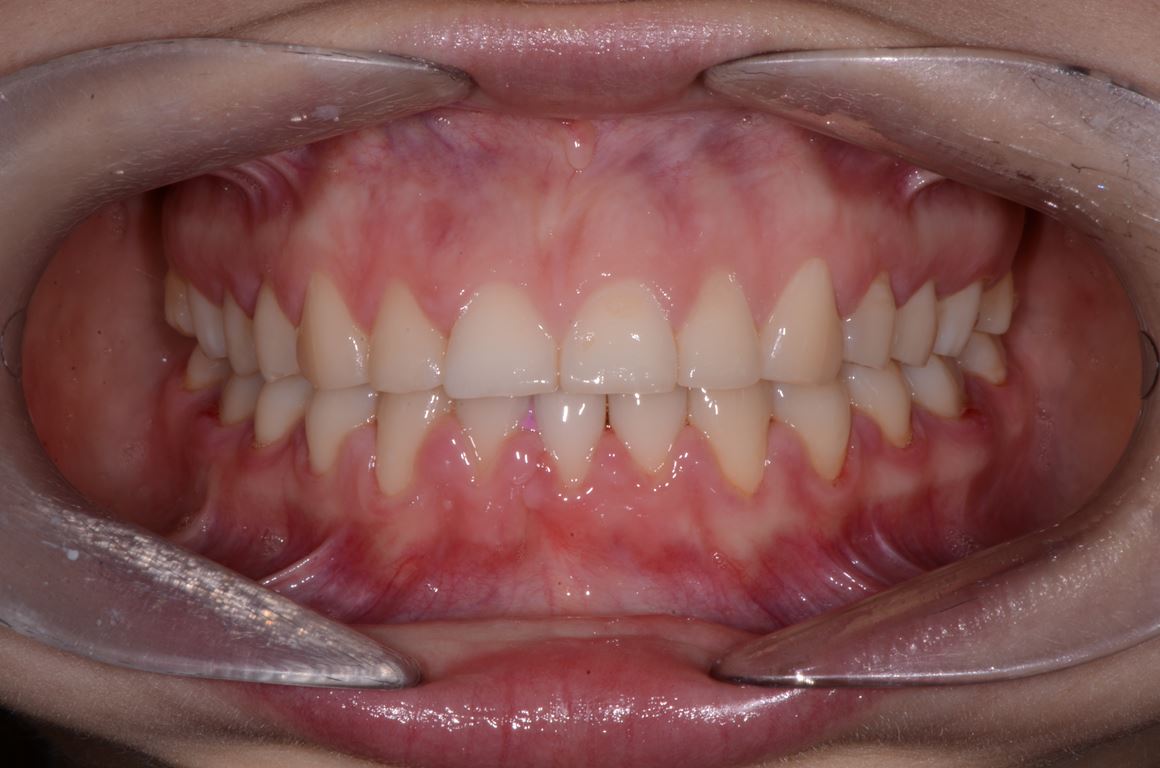

Ryciny 39-50 przedstawiają stan po zakończeniu leczenia.

Drugie zęby trzonowe nie zostały włączone w rekonstrukcję pomimo znacznej utraty wysokości koron. Dzięki temu podniesienie wysokości zwarcia mogło być zminimalizowane oraz uniknięto konieczności preparacji zniszczonych powierzchni zwarciowych tych zębów. Po przebudowie warunków zwarciowych na pozostałych zębach uzyskano prowadzenie przednie i kłowe, co potencjalnie dało ochronę zębów trzonowych przed destrukcyjnymi siłami bocznymi.